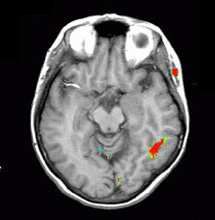

| Activation |

Left hemisphere activation is clearly greater. The activation is in the following areas: Broca's (image 5), Wernike's (images 4 and 5), left supramarginal gyrus (heteromodal associative area, in image 5), left motor and premotor strip. The primary auditory areas are also activated predominantly on the left. |